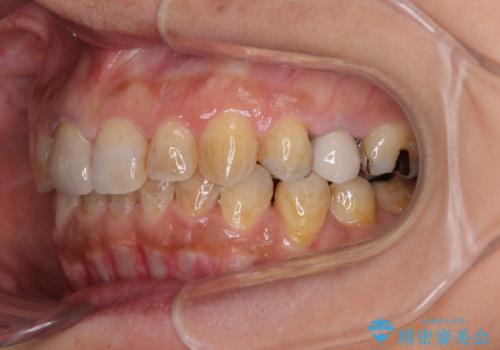

- 上下前歯のデコボコと、治療途中の歯を気にして来院された患者様です。

ご家族がインビザラインにて矯正治療を行っていたため、ご本人の希望によりインビザラインによるマウスピース矯正を行うこととしました。

根管治療が必要な歯は事前に処置を行った上で矯正治療を開始し、概ね歯列が整ったところでセラミッククラウンなどに置き換え、その後インビザラインを1セット使用して仕上げていくこととしました。